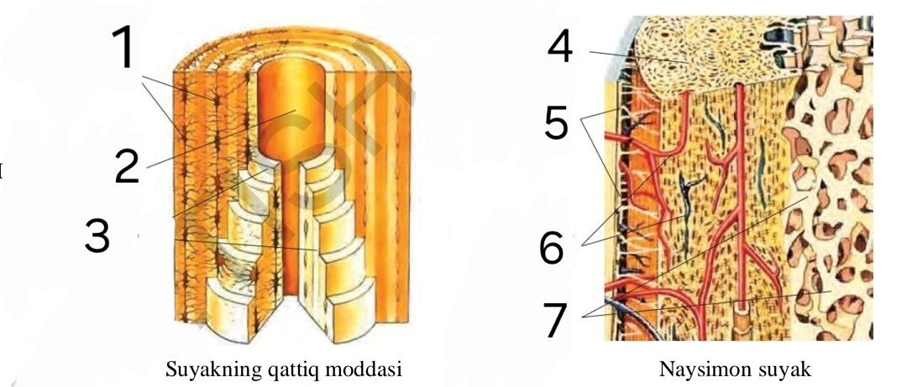

3-topshiriq. Ma’lumotlarni rasmlarga mos raqamlang.

Quyidagi rasmda suyakning mikroskopik tuzilishi aks ettirilgan. Ushbu rasmdagi raqamlarni ma’lumotlarga mos juftlang.